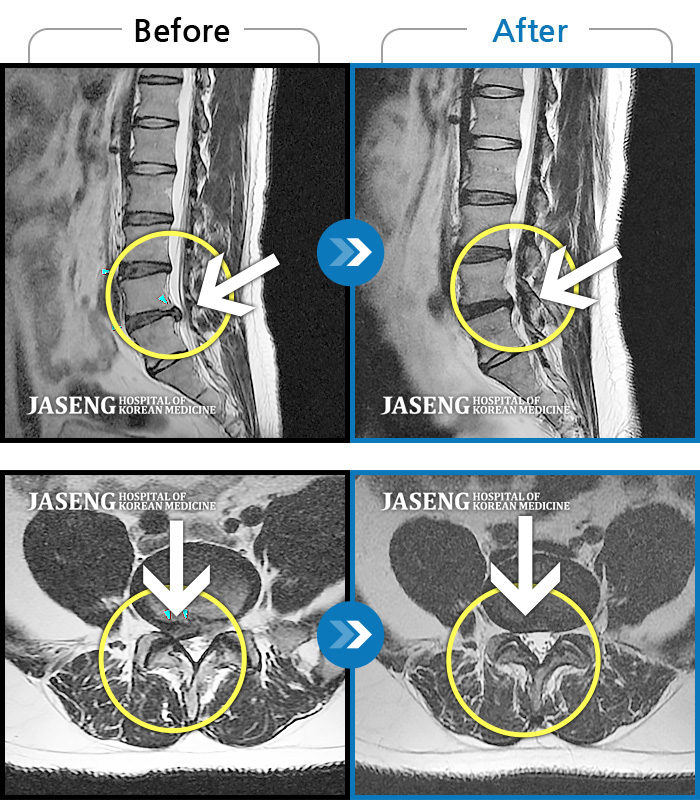

허리디스크

보라매 · 빈상은 원장

엉치에서 좌측 다리 뒤쪽으로 통증과 저림이 매우 심해요.

촬영시기

2024.06.08 ~ 2024.08.31

2024.12.24

조회수 410